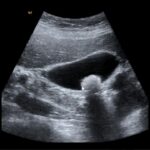

Sofro de transtorno diageneralizada, sou muito agitada e tenho um casamento muito conflituoso. Foi diagnosticado no início do ano com dois cálculos de vesícula. Ele disse que fiz exames de sangue e nenhuma alteração orgânica foi encontrada. Aliás, o cálculo de vesícula não é fácil saber a causa, não se encontra a causa e vão cristalizando no interior da vesícula biliar. Alguns cálculos e não sabe por que exatamente, por isso que eles removem a vesícula. Não adianta extrair o cálculo se você não resolve o que está causando o cálculo fisicamente falando. Metafisicamente, nós falamos em seguida o médico inclusive, e ele não sabe, não soube explicar a formação do problema. Já tive cálculo nos rins e agora na vesícula. A única causa é que ele pergunta não é a psiquê e as emoções. Como eu explico aqui é que vai encaminhando a manifestação no físico.

Sempre que há um mal físico, existe um agente orgânico causador. A metafísica da saúde ela estuda as causas, mas não isoladas do físico. Uma hora, a medicina vai encontrar o que causa estas cristalizações. Por exemplo, nos rins, existe uma aglomeração exagerada de cálculo. Tanto quando a pessoa tem excesso de cálcio na urina, esse excesso de cálcio na urina é propenso a causar pedras nos rins.